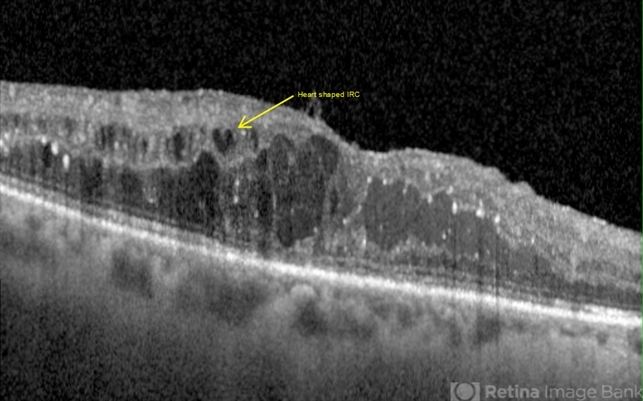

- diabetic macular edema, intraretinal cyst

- Horizontal OCT scan of a 63-year-old woman with diabetic macular edema in the right eye. When reviewing the scan, one of the intraretinal cyst (IRC) appears heart shaped. A fun scan to see just a few day's before Valentine's day.